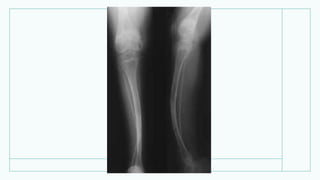

• Рентгенограмма нижніх

кінцівок дитини 1 року 4

місяців: типова рахітична

деформація

великогомілкових кісток.